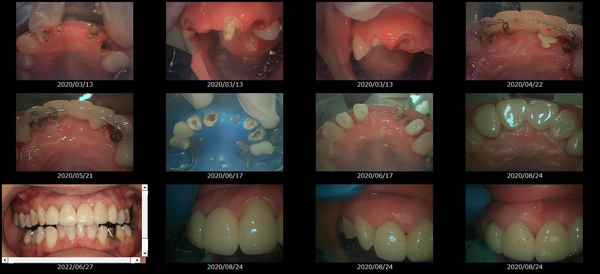

歯の形、歯並び、歯肉ラインが整う美しい口元

大掛かりな歯ぐきの手術や装置を使った矯正治療を行わずに、たった2回で歯並びをきれいに整えることができます。

術前

-

術後

BTAテクニック® とは

従来のセラミックで治すオールセラミックという被せ物や、セラミックを張り付けるラミネートべニアという方法に、歯科医師と歯科技工士の双方の手法と技法を癒合させることで、可能とした 歯ぐきのラインを2回の来院で、綺麗に仕上げ、歯の見た目も審美的に出来るテクニックのことである。

BTAテクニック® 以外の一般的な治療で歯ぐきのラインを整えるには、歯ぐきを切り、骨を削る手術をすれば可能ですが、歯ぐきの治りに数か月の期間が必要です。もしくは、矯正治療によって、歯並びを改善する方法、もしくは神経を抜いて、被せ物をするしかありません。

BTAテクニック® を用いると、歯ぐきや骨への手術が必要ない為に、治療期間が短縮でき、2回の来院で完了できるメリットがある。 また、この方法を用いることで、年々歯ぐきが下がって見た目が悪くなるということが起きにくくなる。歯周ポケットと言われる溝が浅くなり、歯ブラシが容易になる。などの利点が挙げられる特殊なテクニックである。

また、救歯BTAセラミックは、BTAテクニック®が持つ成功する理由(*)から、深い位置まで虫歯が進行してしまって歯を抜かないとならない歯に応用する事で、抜かずに治療することが出来る場合がある。

症例によっては、BTAテクニック® , 救歯セラミックが適応出来ない場合があります。 また、この方法を用いることで必ず歯が残せるという治療方法ではありません。